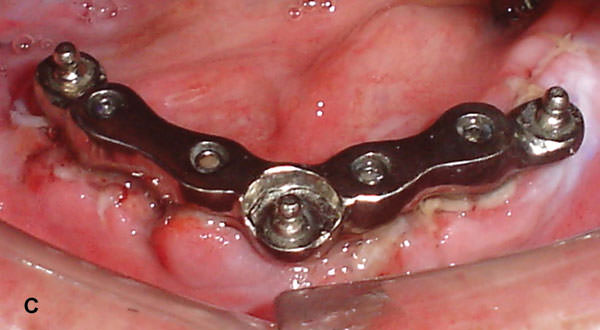

Como descrito por Lederman 41-42 y Graber & Besimo 43, una conexión rígida por medio de una barra en forma de U unida 3 ó 4 implantes inter-foramen podría reducir macro-movimientos, como en la situación de una sobredentadura con carga inmediata.

Estudios y relatos clínicos muestran que la oseointegración normalmente ocurre cuando los implantes son cargados usando conectores rígidos. La función de las estructuras metálicas con fijación ortopédica seria reducir el movimiento y promoción de la integración del tejido óseo al implante 34,44-47.

Gatti et al. 17 realizaron un estudio prospectivo con sobredentaduras mandibulares inmediatas implanto-retenidas por 4 implantes (screw plasma-sprayed ITI-Straumann Institute, Waldenburg, Switzerland). Los implantes fueron inseridos en la región entre los conductos mentonianos foramen y posteriormente ferulizados por una barra de oro o titanio en forma de U. Los autores observaron un porcentaje de manutención de 96%.

Diversos trabajos utilizaron 4 implantes conectados por una barra rígida para soportar sobredentaduras mandibulares con carga inmediata 15-17 y fueron obtenidos altos índices de éxito de los implantes.

Figura 7C